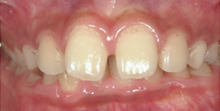

上顎前突(じょうがくぜんとつ)

いわゆる「出っ歯」の状態。前歯がかみ合わず、食事や、滑舌に影響したり口が閉じにくい為、

乾燥してむし歯や歯周病になりやすくなります。 -